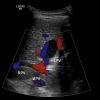

Phình TM cửa

» Thông tin: Nam giới – 90 tuổi.

» Lâm sàng: Kiểm tra sức khỏe.